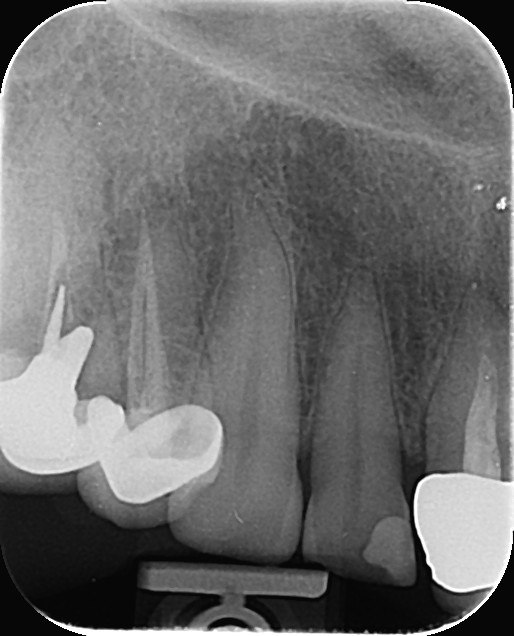

3. What is the caries level on the distal surface of the tooth # 3.6?

6: What is the caries level of mesial of the tooth # 3.6?

7: What is the caries level of Distal of the tooth # 3.6?

11. What is the caries level of the distal surface of the toot # 3.5?

16. What are the caries level in mesial and distal surfaces of the tooth # 4.6 respectively?

17. What is the Caries level on distal surface of the tooth # 3.5?

19. What are the caries level in mesial surface of tooth # 3.8 and distal surface of tooth # 3.7 respectively?

20. What is the caries level in distal root surface of the tooth # 2.5?

21. What is the caries on mesial surface of tooth # 2.7?

22. What is the caries level of distal surface of tooth # 3.3?

23. What is the caries on distal surface of the tooth #2.4?

24. What are the caries level in distal surface th # 4.4, Mesial surface tooth # 4.5 respectively?

25. What are the caries level in distal surface of the tooth # 1.4, Mesial surface of the tooth # 1.5 respectively?

26. What are the caries on distal surface of the tooth # 4.6 and mesial surface of the tooth # 4.7?

27.  what is the condition of the distal surface of the tooth # 4.5?

28. What are the coditions in the distal surface of the tooth # 4.5 and mesial surface f the tooth # 4.7 respectively?

29. What is the condition of the distal surface of the tooth # 4.7?

30. What are the conditions in the distal root surface of the tooth # 3.7 and distal root surface of the tooth # 3.8 respectively?

31. What is the condition of the occlusal of the tooth surface of the tooth # 4.7?

33. What is the caries level of the distal surface of the tooth # 1.6?

34. What is the proper tretment for mesial surface of the tooth # 1.6?

35. What is the condition of the distal surface of the tooth # 4.7?

36. What is the caries level of the distal surface of the tooth # 3.4 and mesial surface of the tooth # 3.5 respectively?

37. What is the caries level of distal of the tooth # 3.6?

39. What are the caries level in distal surface of the tooth # 3.4 and mesial surface of the tooth # 3.5?

41. Which surface shows root caries?

44. What is the caries level of mesial of the toth # 1.6?